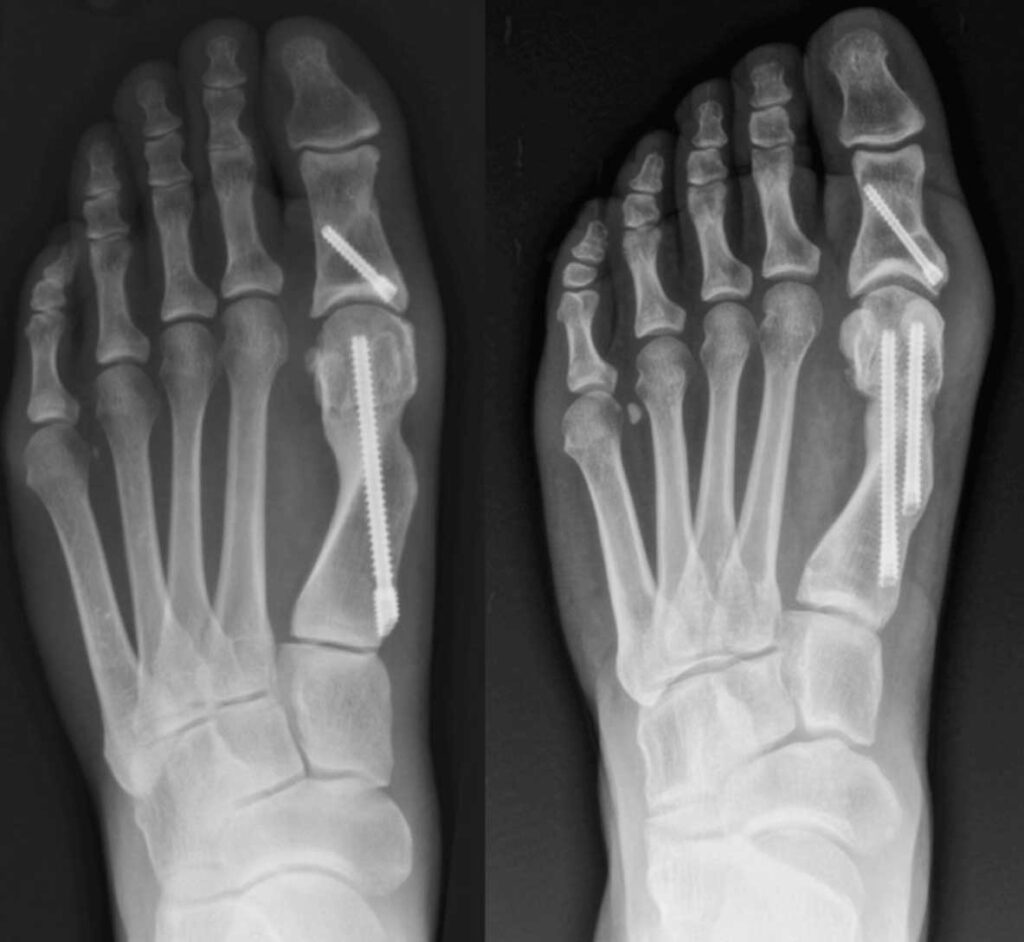

Radiographs demonstrating single-screw (left) and dual-screw (right) fixation following minimally invasive distal metatarsal osteotomy for hallux valgus correction.

Minimally invasive surgery (MIS) for hallux valgus has evolved significantly, with ongoing debate about optimal fixation methods. Fourth-generation techniques typically use 2 metatarsal screws; however, single screw fixation may reduce operative time, radiation exposure, and cost. This systematic review compares clinical outcomes, radiographic results, and complications between 1- and 2-screw metatarsal fixation in minimally invasive hallux valgus correction. Risk of bias was assessed using the Risk Of Bias in Non-randomized Studies of Interventions (ROBINS-I) tool. Primary outcomes included radiographic parameters (Hallux Valgus Angle (HVA), Intermetatarsal Angle (IMA), Distal Metatarsal Articular Angle (DMAA)) and clinical outcomes American Orthopaedic Foot & Ankle Society Score (AOFAS), Visual Analog Scale (VAS), Manchester-Oxford Foot Questionnaire (MOXFQ)). Secondary outcomes included operative details, complications, and revision surgery rates. Five studies met inclusion criteria: 2 clinical (n = 153 patients, 162 feet) and 3 biomechanical studies. Clinical studies showed comparable radiographic correction and patient-reported outcomes between fixation methods. Single screw fixation demonstrated significantly shorter operative time and reduced fluoroscopy exposure. Hardware-related complications requiring removal were higher in 2-screw groups (32% vs. 3% in one study; 1.9% vs. 0% in another). Biomechanical studies revealed that single screw fixation may provide insufficient rotational stability, while 2-screw configurations demonstrated improved construct stability. Current evidence suggests that single screw fixation may reduce radiation exposure, surgical time, and hardware removal rates, but offers reduced biomechanical stability compared to a 2-screw construct in patients undergoing minimally invasive hallux valgus surgery. Current evidence is insufficient to establish definitive recommendations, and fixation strategy should be individualized based on deformity characteristics and patient factors.